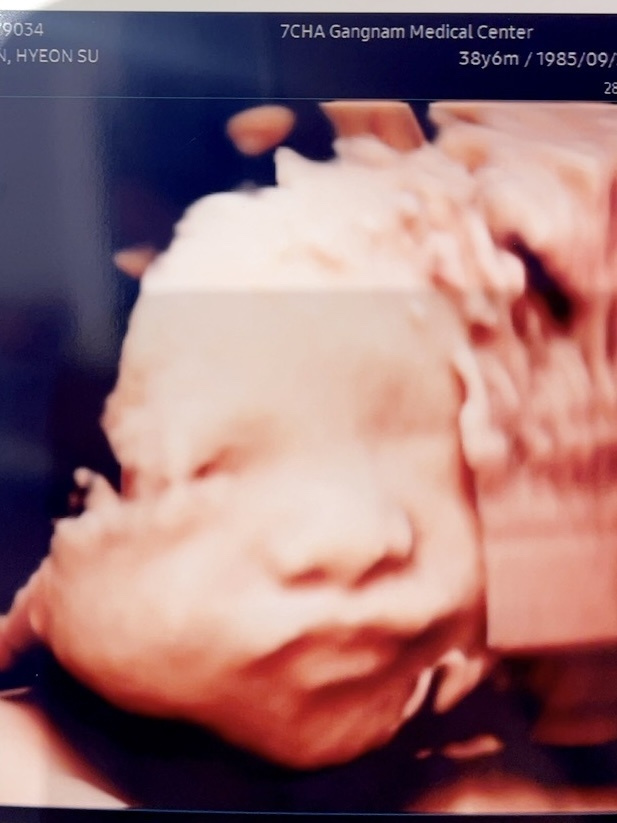

지난해 아내 배 속에 있는 아기의 초음파 사진을 보며 금연을 결심했다. 하찮아 보이는 이 존재한테 담배 냄새가 스며들면 해로울까 봐 염려됐기 때문이다. 육아휴직 중에는 술도 안 마시기로 했다. 건강을 위한 목적도 있지만, 체력과 정신력의 부침 없이 육아에 전념하고 싶은 마음 때문이었다. 다른 이의 강요 없는, 온전히 스스로 내린 결정이었다.